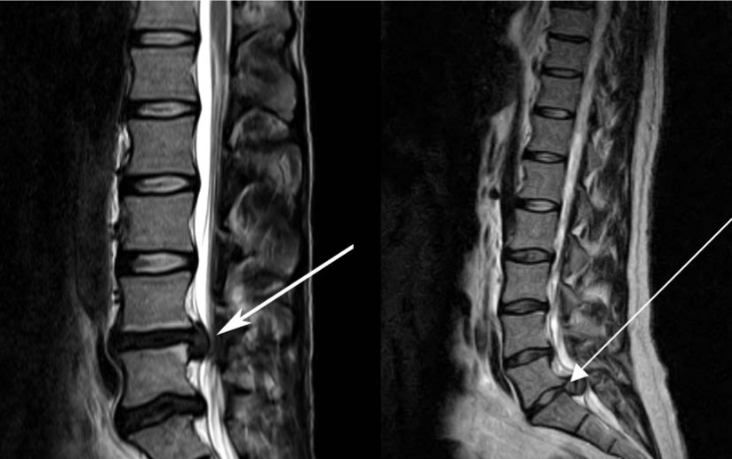

Hình 2: MRI cho thấy hình ảnh khối thoát vị gây HCCĐN [3]

Bên trái: thoát vị L4-L5

Bên phải: thoát vị L5-S1